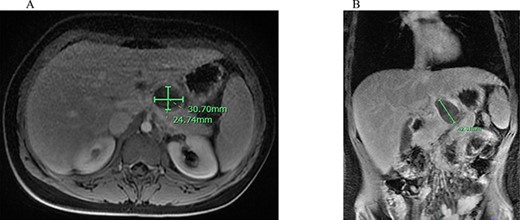

An abdominal ultrasound (US) demonstrated a peripancreatic cystic mass with internal debris located between the stomach and pancreas (Fig. 1). The differential diagnosis at that time included a foregut duplication cyst, an infradiaphragmatic sequestration and a pancreatic cystic lesion. Given the unclear origin of this lesion, an abdominal magnetic resonance imaging (MRI) was obtained, which identified a T1 hypointense and T2 hyperintense rim enhancing 4.3-cm mass with surrounding edema and adjacent peripancreatic inflammation (Fig. 2).

Abdominal MRI of suspicious mass; (A) axial abdominal MRI revealing 3.07 × 2.74 cm mass (green bars) posterior to the L. lobe of the liver and medial to the stomach; (B) coronal abdominal MRI demonstrating 4.26 cm mass (green bar) inferior to the liver and superior to the pancreas with peripancreatic inflammation.

Liver parenchyma appears homogenous with echogenicity similar to renal cortex and native liver on abdominal US. As an adjunct to US, liver-sequenced MRI can delineate anatomy, vascular supply and intrahepatic pathology. Healthy liver appears uniform, with T1 hypointense and T2 hyperintense signals on MRI [7]. The presence of tissue with these characteristic findings is not diagnostic for EL but may provide some preoperative insight, as was the scenario in this case. The US we obtained was non-diagnostic. Given the broad differential, we obtained an MRI that demonstrated a well-circumscribed T2 hyperintense lesion, which was consistent with an EL rest.